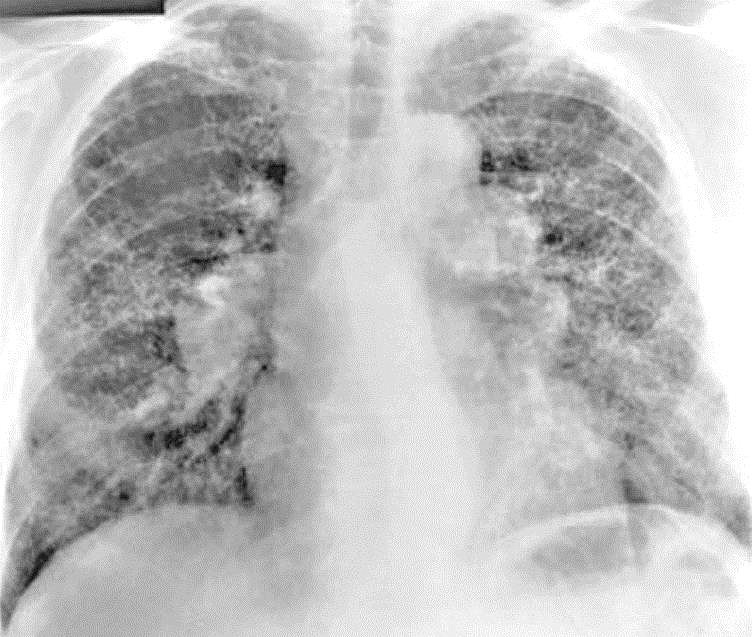

English: 54 year old man who works in the aerospace manufacturing industry. Berylliosis an occupational lung disease that is usually associated with aerospace manufacturing, beryllium mining or manufacturing of fluorescent light bulbs (which used to contain beryllium compounds in their internal phosphor coating).

Contributed by Dr. Mark Wick